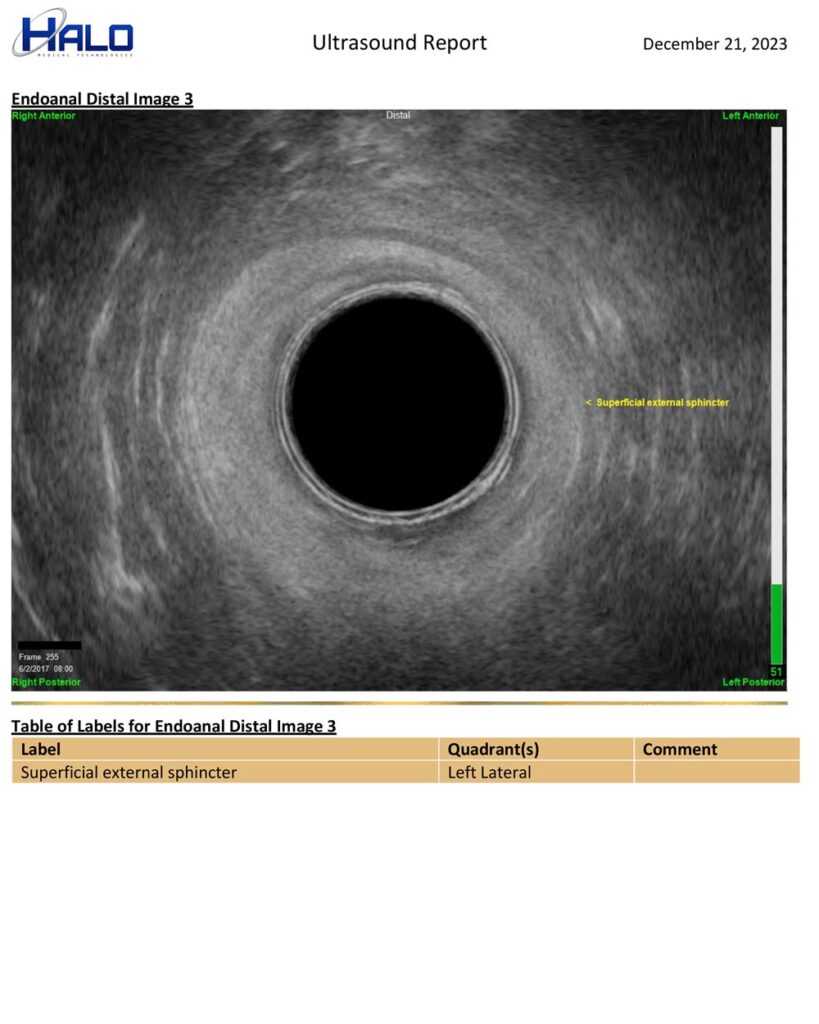

EZ-Reporter Auto-Generated Ultrasound Reports

Perform exams, mark/measure images, & document your interpretation. EZ-Reporter does the rest. The final report is auto-populated with your findings and ready for your patient’s medical record or to be sent to a referring clinician.

Sample Report